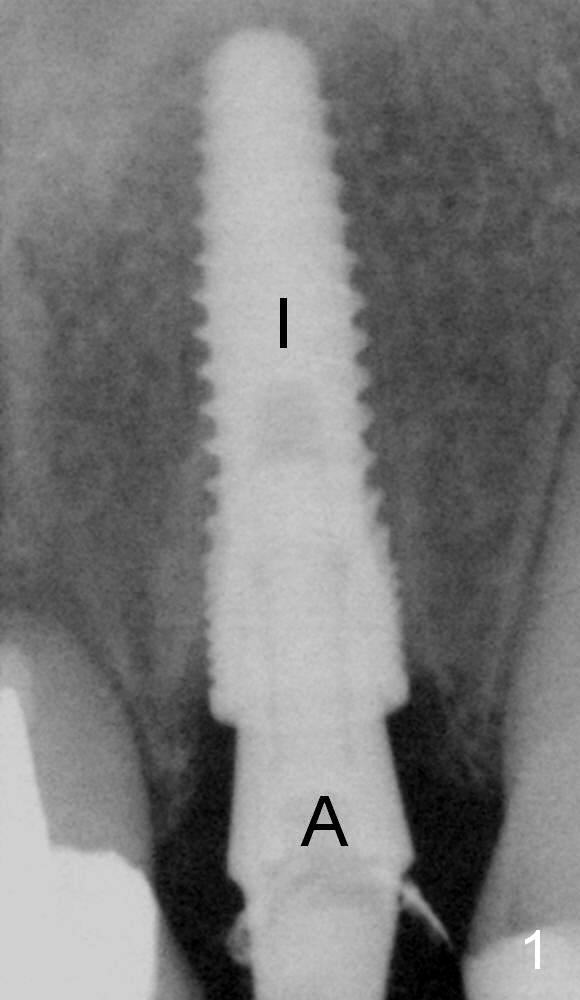

Fig.1,2 show the abutment (A) before and after torquing, respectively.  After the torquing, the abutment turns mesially (Fig.2 white arrow) and apparently ascends slightly (black arrow).  The height of the space inside the implant (I) is shortened after torquing (compare Fig.1,2).  In other word, the abutment was incompletely seated prior to torquing.